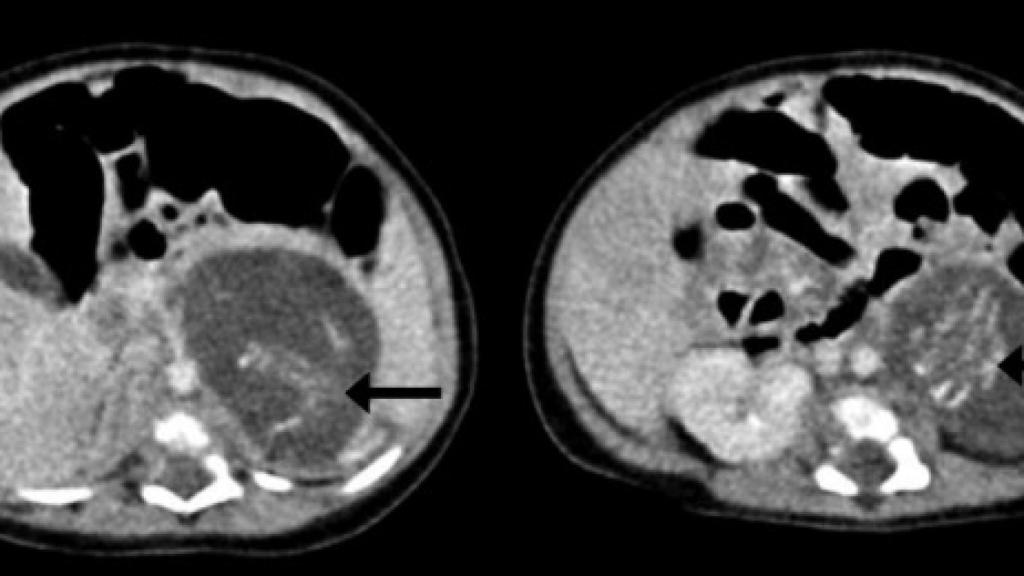

En 2010, en un hospital de Hong Kong ocurrió algo que sólo se da en uno de cada 500.000 nacimientos: una menor nació con dos masas anómalas en el estómago. Años después, en un informe presentado en la revista Honk Kong Medical Journal por el doctor Yu Kai-man, del Hospital Queen Elizabeth de Hong Kong, se ha concluido que estas dos masas eran dos fetos gemelos con un peso de 14,2 gramos y 9,3 gramos, respectivamente.

Lo que le ocurrió a esta niña bebé es lo que en términos médicos se conoce como fetus in fetu. Consiste en la aparición de fetos no desarrollados en forma de tumor en alguna parte de la anatomía de un recién nacido. Suele producirse por un fallo en la formación del cigoto antes de la formación del embrión, lo que conlleva que rara vez tenga órganos internos funcionales. El 80% de las veces los fetos se encuentram en la región abdominal, pero también pueden encontrarse en el cráneo, zona sacra, escroto, etc.

En el caso aparecido en China, los fetos tenían formadas las piernas, los brazos, la columna y parte de los intestinos. Ambos estaban unidos por el cordón umbilical al abdomen de la menor. Como indica el experto que ha realizado el diagnóstico en el diario Mirror, en realidad los gemelos son de los padres pero el proceso de fertilización ocurrió por el lado equivocado.

A juzgar por las partes del cuerpo que encontraron en la niña, los médicos han determinado que los gemelos absorbidos podrían tener hasta 10 semanas de gestación antes de que su crecimiento se detuviera y fueran absorbidos. Pero el mecanismo de esta “absorción” no se ha dilucidado, por lo que también es posible que los fetos adicionales hubieran sido absorbidos anteriormente a la nueva gestación.